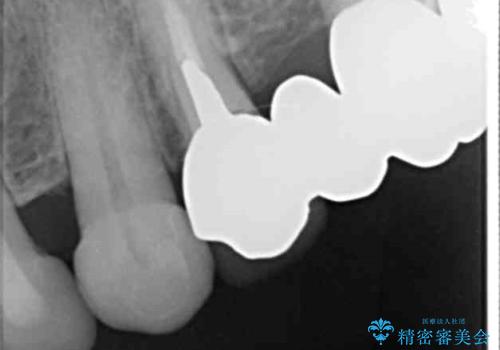

- 前歯のセラミック治療から4年半経過した患者様です。

4年ぶりに来院して下さいました。

治療した上の前歯6本は全く問題なく、「獅子舞みたいだった前歯を綺麗にして下さってありがとうございました!」と再度お礼を言って下さいました。

4年半前のクラウン装着時と変わらず、まるで天然歯のように自然に見えました。

患者様の良好なセルフケアと精密な適合の良いクラウンにより、歯肉の腫脹や退縮も認められませんでした。